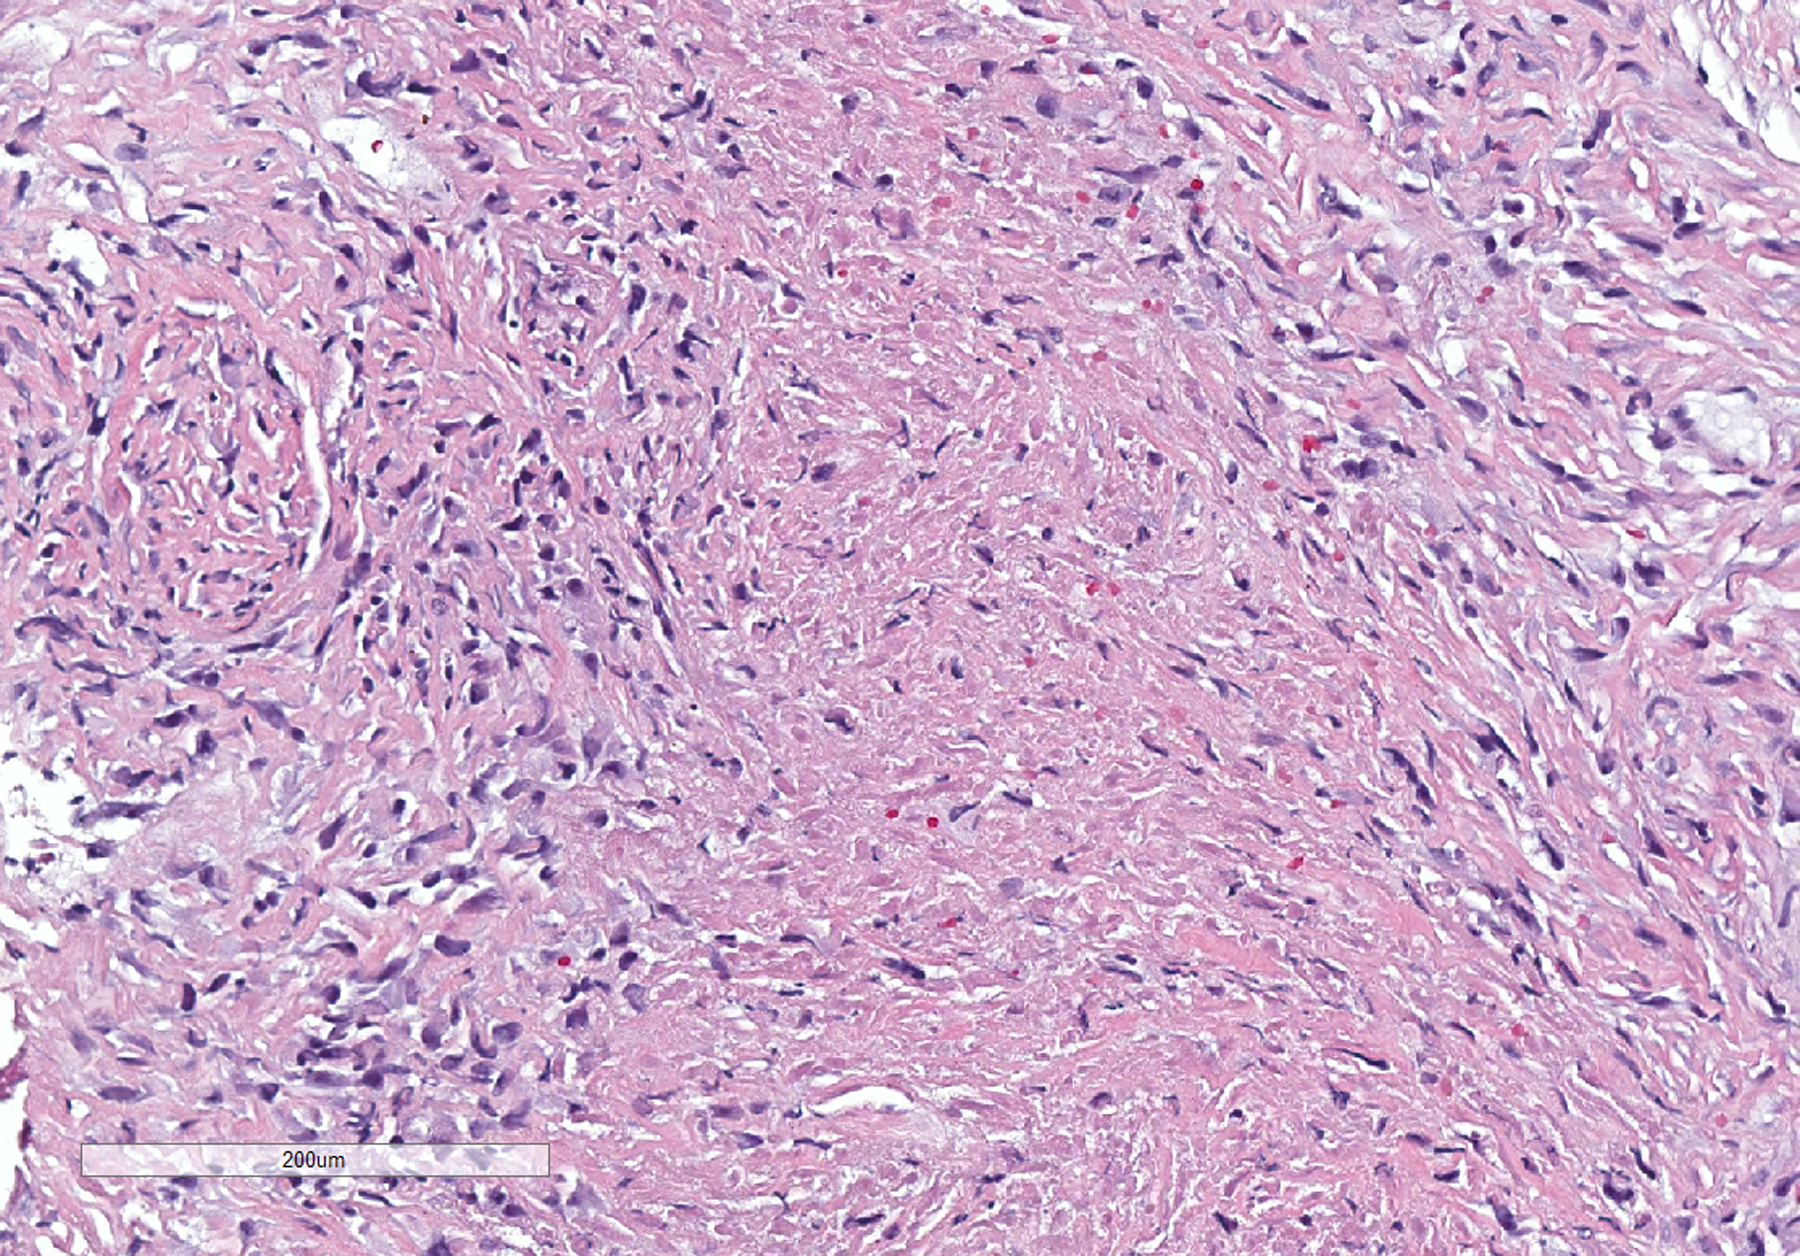

Sarcomatoid mesotheliomas can be challenging to diagnose on small biopsy specimens, where limited material may preclude definitive assessment of invasion and lesional cells can have relatively bland cytology with no mesothelial marker expression. We report a case of a patient who presented with a pleural effusion and had subsequent pleural biopsy that showed a bland, uniform spindle cell proliferation in a mildly myxoid background. There was little if any collagen; no chest wall, soft tissue, or fat; and mesothelial markers were negative. The cells were positive for pancytokeratin and GATA3 by immunohistochemistry, and in situ hybridization showed a "negative" result for homozygous loss of CDKN2A; however, there was partial (heterozygous) loss of one allele. A diagnosis of atypical spindle cell proliferation was made based on these findings. Several months later, the patient had a repeat pleural biopsy that showed spindled cells with more pleomorphism, areas of invasion into the chest wall, and the same partial loss of CDKN2A, consistent with a sarcomatoid mesothelioma. This case underscores the challenges present on small biopsy specimens, the fact that sarcomatoid mesotheliomas can be relatively bland appearing with focal pleomorphism, and that heterozygous loss of CDKN2A should be considered a positive result indicative of a neoplastic process.